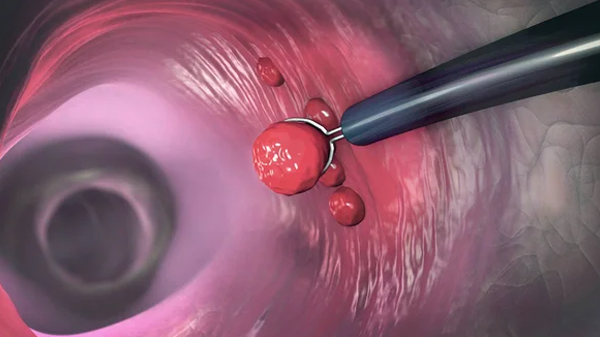

a polipectomía endoscópica es un procedimiento médico en el cual se extirpan los pólipos que se encuentran en el tracto gastrointestinal utilizando un endoscopio. Los pólipos son crecimientos anormales que pueden aparecer en la superficie del revestimiento del estómago, colon o recto.

Durante la polipectomía endoscópica, se introduce un endoscopio flexible a través de la boca (para el estómago) o el recto (para el colon y recto) para visualizar la superficie del tejido intestinal. Luego, se utiliza un instrumento especial para cortar y extirpar el pólipo de la superficie intestinal. Este procedimiento se realiza generalmente bajo sedación y puede durar entre 30 minutos y una hora.

La polipectomía endoscópica es un procedimiento importante para detectar y prevenir el cáncer colorrectal, ya que los pólipos pueden ser precursores del cáncer. También se utiliza para tratar los pólipos grandes o aquellos que se sospecha que son malignos.

En resumen, la polipectomía endoscópica es un procedimiento médico que se utiliza para extirpar los pólipos en el tracto gastrointestinal utilizando un endoscopio. Se realiza para detectar y prevenir el cáncer colorrectal y para tratar los pólipos grandes o malignos. El procedimiento se realiza bajo sedación y puede durar entre 30 minutos y una hora.